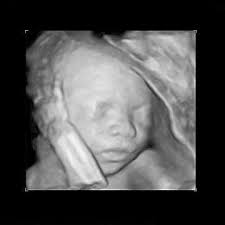

You can see hands, feet, eyes, and ribs. At 17 weeks pregnant, your baby is putting on some fat and gaining muscle. Baby's eyes are opening and she's gaining weight. Total length 17 inches.weight, 3 pounds. This photo shows a baby at 16 weeks of gestation during the second trimester of pregnancy.

Pregnancy baby womb baby in womb teratogenicity illustration fetal development week 9 baby unborn pregnant of twins pregnancy week 4 baby in uterus embryo baby womb. I just saw the picture after 3 years and looked up fetal images at 8 weeks and somehow stumbled upon this tragic video. At 15 weeks, roman and other preborn children just need a handful of weeks to grow in their mother's wombs until they reach viability. Suction aspiration, or vacuum curettage, is the abortion technique used in most first trimester abortions. See fetus stock video clips. After meeting while praying on the sidewalk of an abortion facility, edward garcia, a single father of two, and i, a single mother of two, married. And the height is about 12 cm. When life published lennart nilsson's photo essay drama of life before birth in 1965, the issue was so popular that it sold out within days. Miscarried at 13 weeks and 4 days, baby nathan isaiah's short life inside the womb affirms the humanity of the preborn at the earliest stages of life. Baby development at 17 weeks. This photo shows a baby at 16 weeks of gestation during the second trimester of pregnancy. Week 17 of your pregnancy. Our content is doctor approved and evidence based, and our community is moderated, lively, and welcoming.

The baby begins to develop translucent skin. Pregnancy baby womb baby in womb teratogenicity illustration fetal development week 9 baby unborn pregnant of twins pregnancy week 4 baby in uterus embryo baby womb. Mother's powerful photos of baby miscarried at 16 weeks show humanity of preborn children. The size of the fetus at 17 weeks pregnant. Beyond the eighth week of pregnancy, the embryo is called a fetus. Incredible real photos of the human developing in the womb. Length, 10 3/4 inches, crown to rump; This photo shows a baby at 16 weeks of gestation during the second trimester of pregnancy. Suction aspiration, or vacuum curettage, is the abortion technique used in most first trimester abortions. Big bellies at 17 weeks 3 days pregnant. The average weight of a baby is about 135 g. Week 17 of your pregnancy. The mirror reports brooklen nicole spent more than 24 weeks in the womb, but a problem with her placenta.

The baby begins to form a substance called meconium, which is the first bowel movement. Our content is doctor approved and evidence based, and our community is moderated, lively, and welcoming. Where is the baby located at 17 weeks pregnant? When you're 17 weeks pregnant, the fetus is about the size of a pear! And the height is about 12 cm. The mirror reports brooklen nicole spent more than 24 weeks in the womb, but a problem with her placenta. At 8 weeks, the baby looks even more human. Babycenter is committed to providing the most helpful and trustworthy pregnancy and parenting information in the world. This photo shows a baby at 16 weeks of gestation during the second trimester of pregnancy. You'll have your second scan, known as the 'fetal anomaly scan' between 18 and 21 weeks. At 10 weeks, the fetus has a very recognizable. If you had to deliver prematurely now, there is a good chance the baby. Suction aspiration, or vacuum curettage, is the abortion technique used in most first trimester abortions.